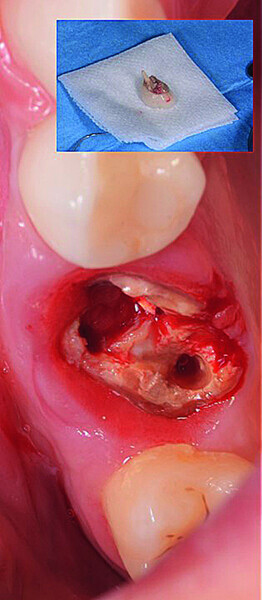

Digital workflow and application of PRF and ozone therapy in oral rehabilitation